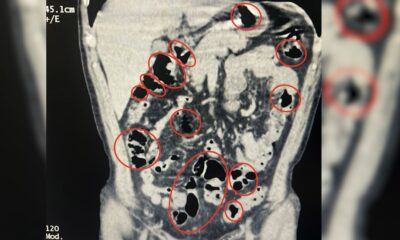

BATMAN’da beyninde kötü huylu tümör tespit edilen Eyüp Ensar Işık (7), Batman Eğitim ve Araştırma Hastanesi’nde yapılan 5 saatlik ameliyatın ardından sağlığına kavuştu. Batman’da yaşayan Gülten...

Batman’da yaşayan Gülten (39) ile Bayram Işık (45) çiftinin 5 çocuğundan Eyüp Ensar Işık’ta, beyin tümörü tespit edildi. Aile, başka hastanelerde tümörün riskli bölgede olduğu gerekçesiyle...